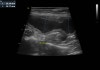

초음파 검사

수술전 복부 초음파검사 / 출처: 라온동물메디컬센터

초음파 검사에서 자궁 내부에 염증성 내용물이 차 있는 소견이 확인되었습니다.